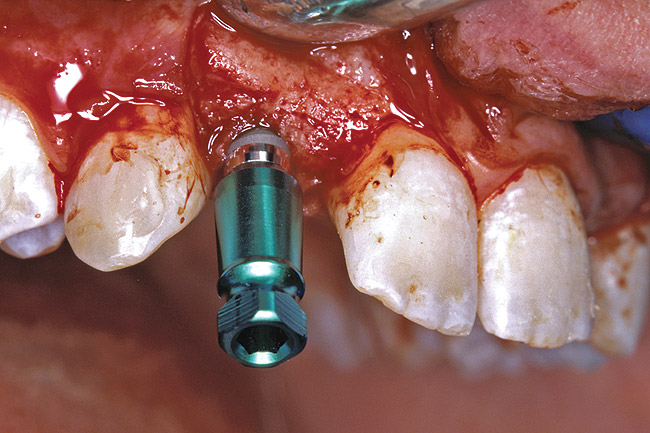

The 3.7-mm diameter Tapered Screw-Vent implant drilling sequence requires three drills: pilot, intermediate, and final sizing. Thus, three separate templates were fabricated to accommodate these sizes. The templates were removed easily and replaced with the next sequential size in less time than it takes to change the drill on the surgical handpiece. After the osteotomies had been completed, the implants were delivered to the site (Figure 33 and Figure 34). For this internal hex connection implant, the author recommends that the flat of the anti-rotational hex be positioned to the facial for proper orientation of the restorative components (Figure 35). Pre-prepared margins were created from a milled titanium fixture mount transfer post, which was delivered to the implant as support for an immediate transitional restoration. The facial “dot” helped to confirm the orientation of the abutment to the facially positioned flat side of the internal hex connection (Figure 36). Before cementation of the transitional acrylic restorations, a closed-tray, fixture-level impression was made, and a soft-tissue model was fabricated.

Figure 33  VIRTUAL PLANNING AND SURGERY After the osteotomies were completed, the implants were placed.

Figure 33

Figure 34  VIRTUAL PLANNING AND SURGERY After the osteotomies were completed, the implants were placed.

Figure 34